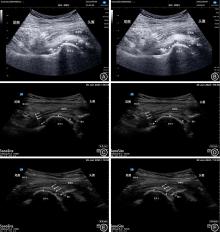

LYNCH T S, OSHLAG B L, BOTTIGLIERI T S, et al. Ultrasound-Guided Hip Injections[J]. J Am Acad Orthop Surg,2019,27(10):e451-e461. doi:10.5435/jaaos-d-17-00908

HOEBER S, ALY A R, ASHWORTH N, et al. Ultrasound-guided hip joint injections are more accurate than landmark-guided injections: A systematic review and meta-analysis[J]. Br J Sports Med,2016,50(7):392-396. doi:10.1136/bjsports-2014-094570

GAO G, FU Q, WU R, et al. Ultrasound and Ultrasound-Guided Hip Injection Have High Accuracy in the Diagnosis of Femoroacetabular Impingement With Atypical Symptoms[J]. Arthroscopy,2021,37(1):128-135. doi:10.1016/j.arthro.2020.08.013